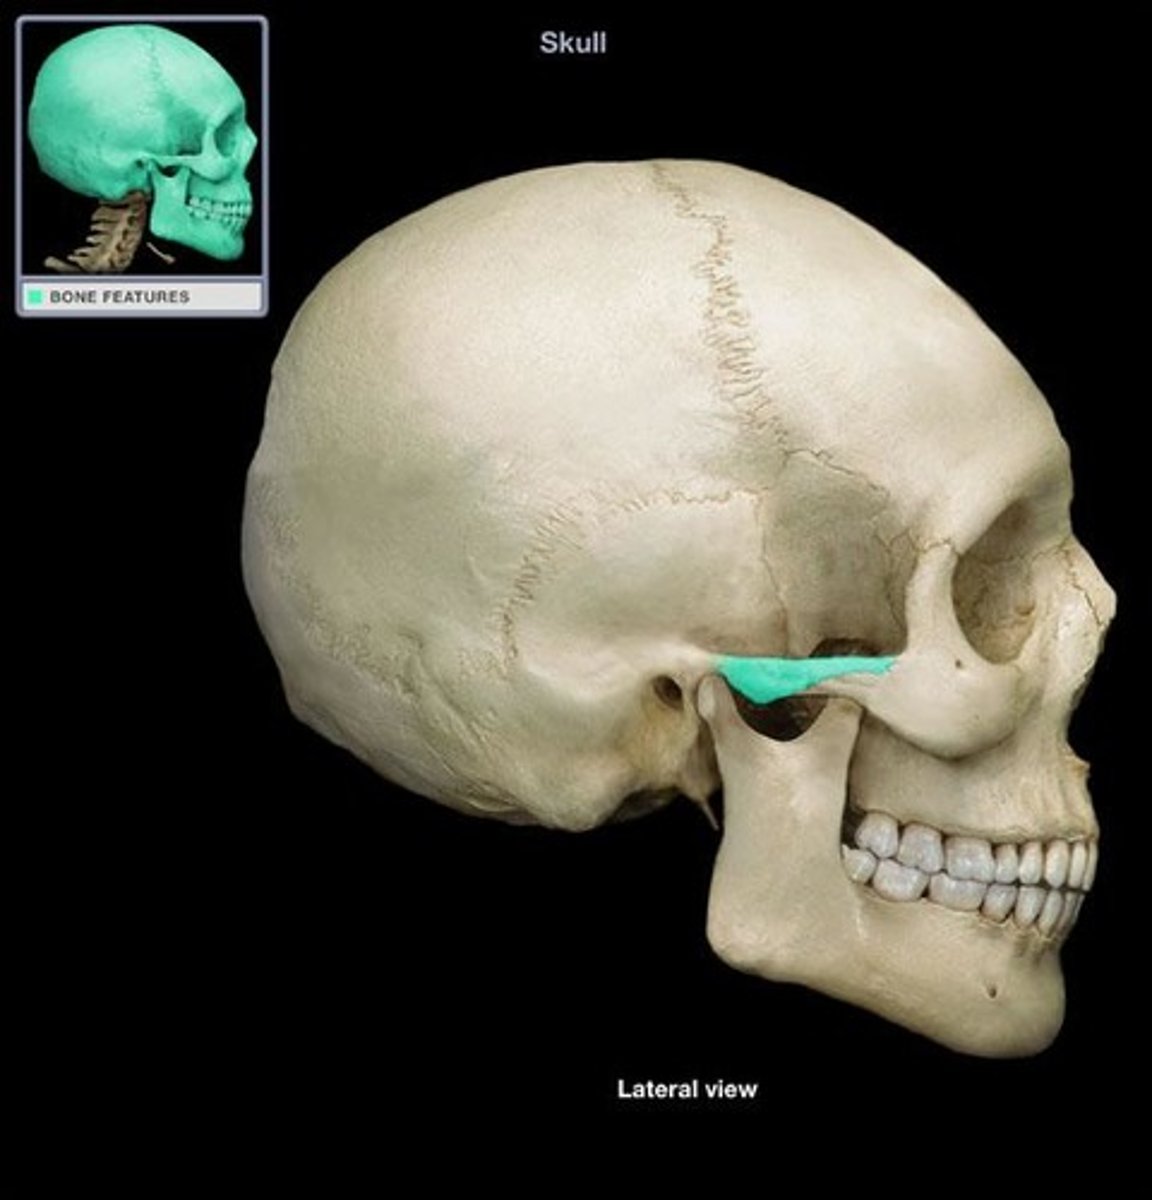

sphenoid bone

greater wing of sphenoid bone

posterior and inferior to lesser wing on the interior of the skull, also visible in the posterior orbit and lateral side of the skull

zygomatic process of temporal bone

extension from the temporal bone that forms the posterior portion of the zygomatic arch, attachment point for temporal fascia

temporal process of zygomatic bone

short extension from the zygomatic bone that forms the anterior portion of the zygomatic arch

pterion

Junction of frontal, parietal, sphenoid, and temporal bones. Structural vulnerability as it is thin and middle meningeal artery is just deep, so hard head blow can result in subdural hematoma